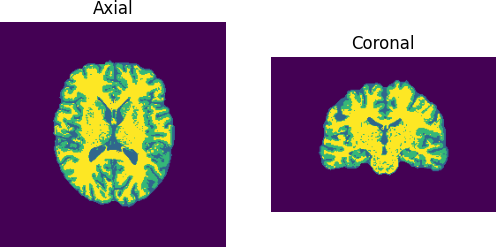

Now we plot the resulting segmentation.

Total time: 38.97768211364746

Each tissue class is color coded separately, red for the WM, yellow for the GM and light blue for the CSF.